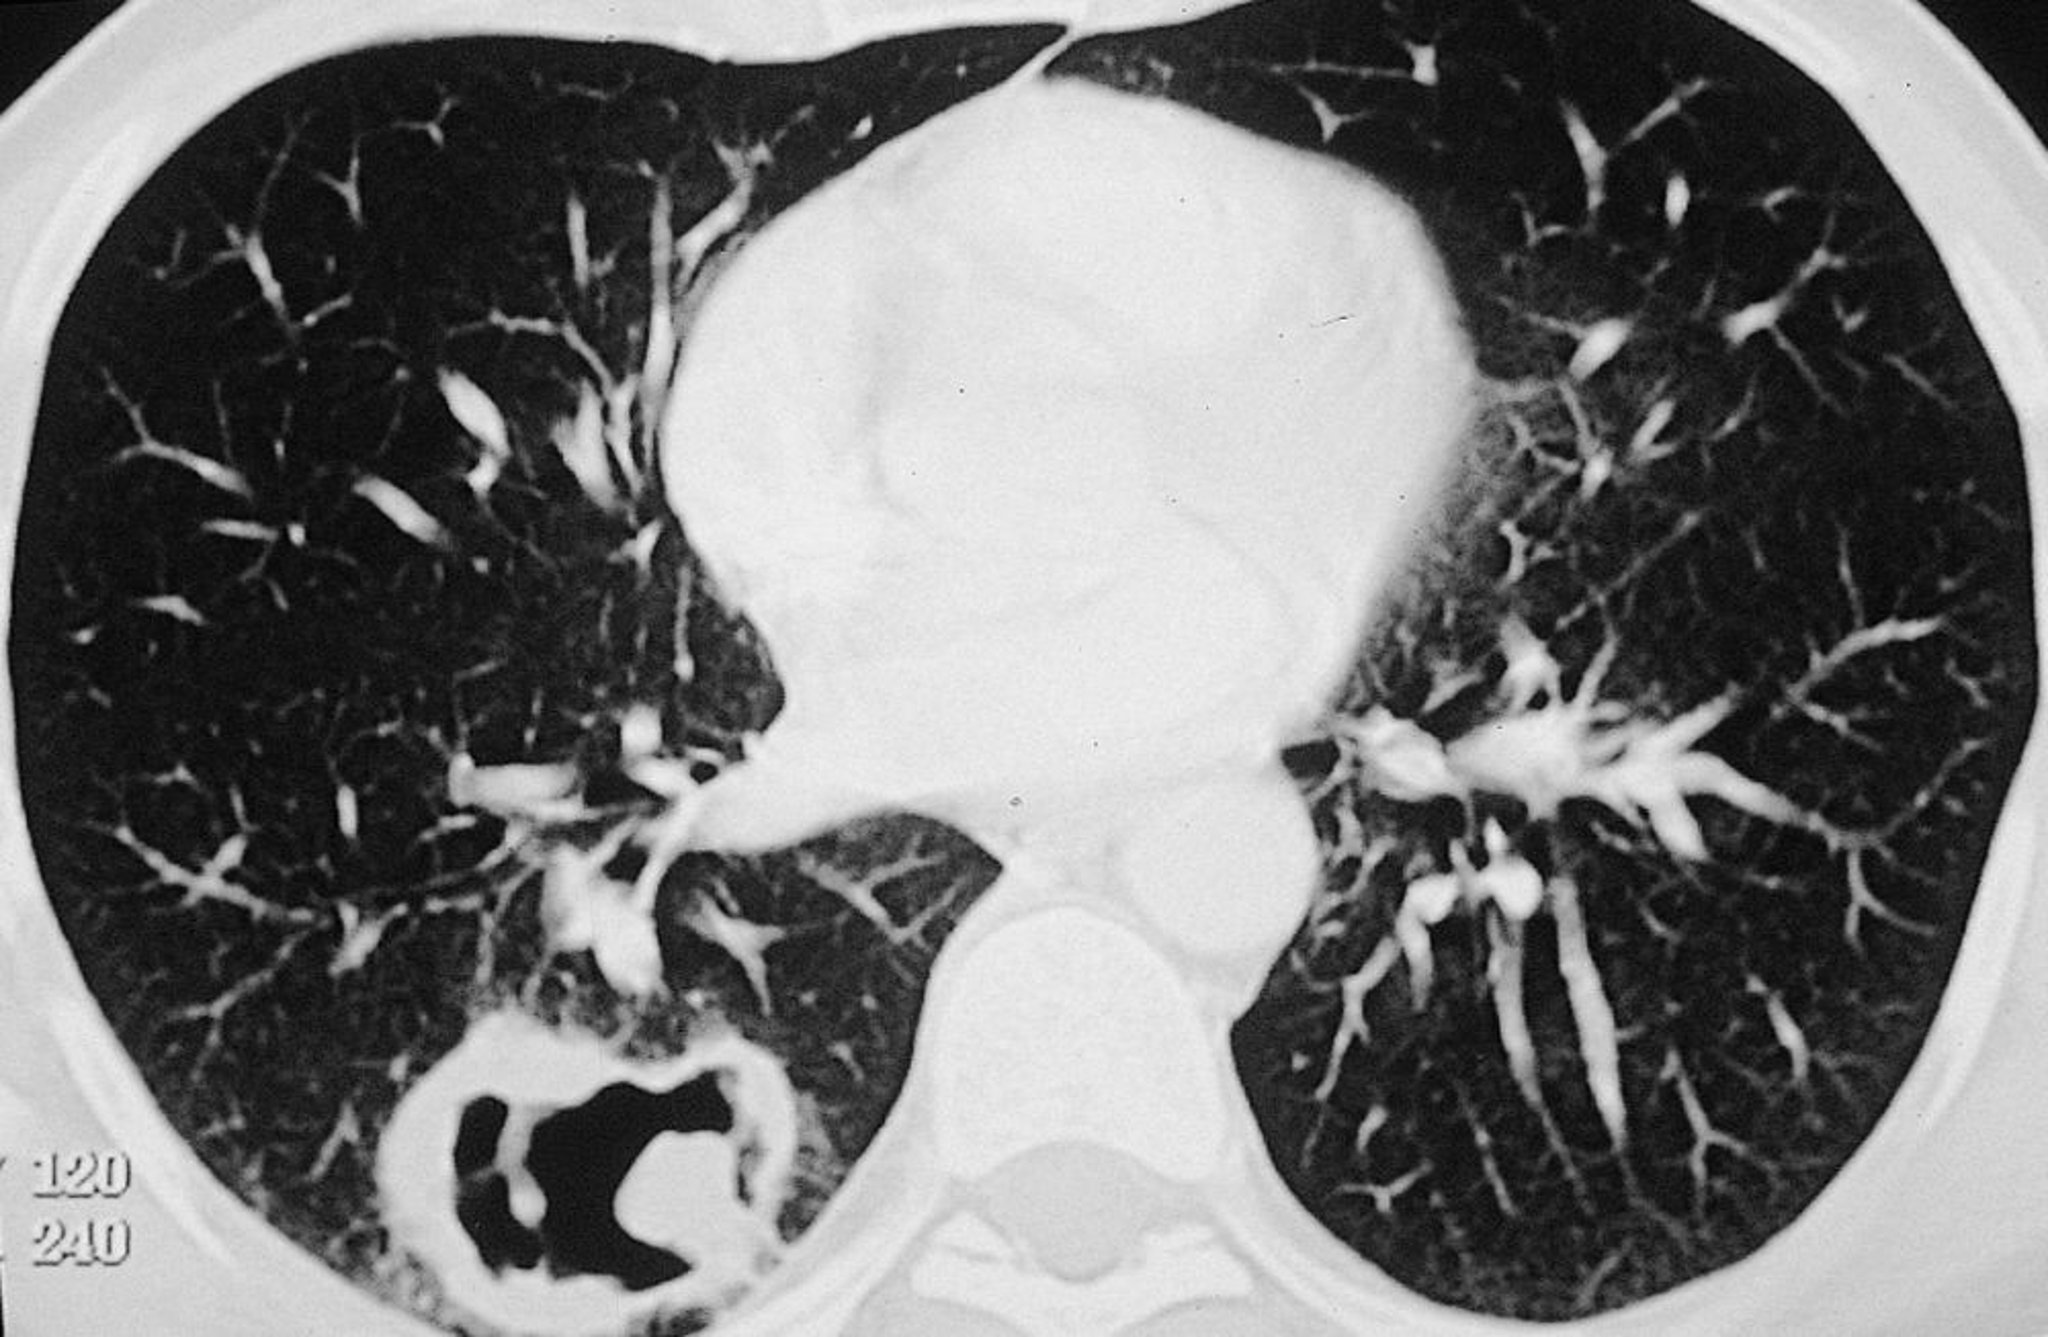

Granulomatosis con poliangeítis (lesión pulmonar)

Lesión cavitaria grande en el pulmón derecho en un paciente con granulomatosis con poliangeítis.